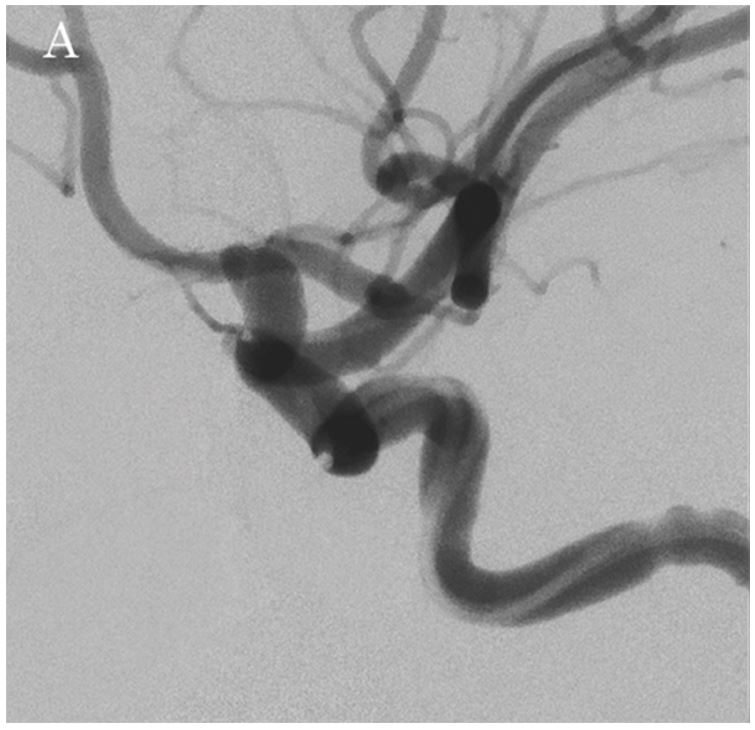

Кут роботи (WA) визначався за допомогою 3D-цифрової субтракційної ангіографії (DSA), для візуалізації нерозірваної аневризми лівої внутрішньої сонної артерії (малюнок 1А).

Було необхідно встановити стент з початку передньої хореоїдної артерії до C3-4 (класифікація Фішера), тому було вибрано LVIS (4,0 мм × 17 мм; Terumo Corporation, Японія). Процедура проводилась за допомогою техніки "jailing",1) в якій мікрокатетер для емболізації вводиться в аневризму перед встановленням LVIS. В якості якоря для навігації мікрокатетера використовувався Axium™ Prime Frame (5 мм × 10 мм; Medtronic Japan Co., Ltd., Японія), після чого було встановлено LVIS.

Флюорографічні зображення, отримані за допомогою Hi-Def Detector, дозволили чітко спостерігати поведінку котушки та мікрокатетера, а також розгортання стенту за допомогою високороздільних зображень, що забезпечило надзвичайно ефективну підтримку під час процедури (малюнки 2A та 2B). Далі, за допомогою опції Alpha CT (конусно-променевої комп'ютерної томографії), було підтверджено стан розгортання стенту та затискування головної судини (малюнки 3А та 3В), після чого проведено додаткову емболізацію з використанням спіральних котушок в зоні втікання до аневризми. Лікування було завершено із щільністю запаковування котушкою у 28,24%. Наявність або відсутність інтранкраніального крововиливу було підтверджено за допомогою Alpha CT.

Малюнок: 1А: Передопераційне DSA зображення лівої внутрішньої сонної артерії.